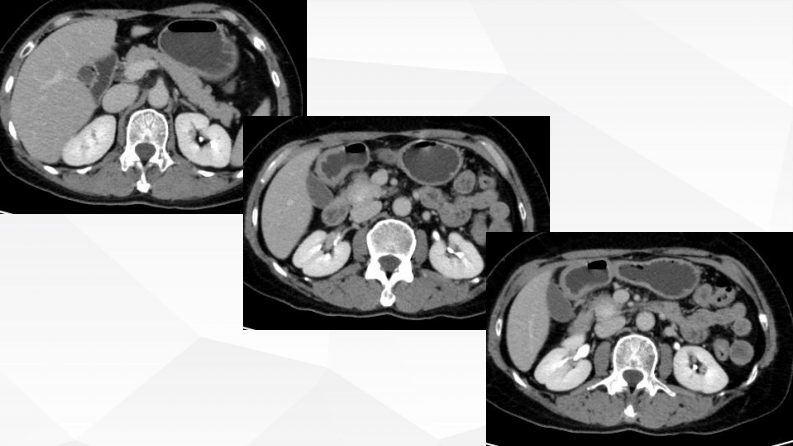

胰腺富血供占位诊断及鉴别诊断--张欢.pdf